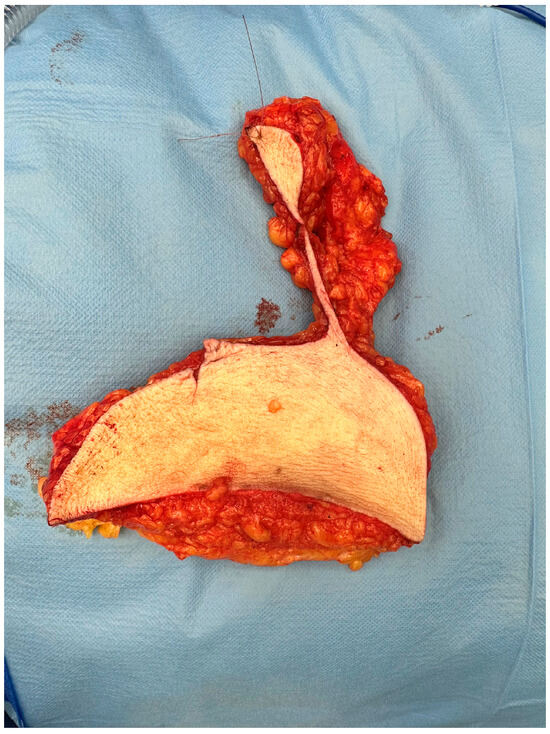

2.3. Pathology: Protocol and Methods

The pathology protocol changes involved inking the reduction preparations of patients with a previous breast malignancy and in patients above the age of 50 (Figure 2). Additionally, the transected slices at grossing are saved in their original order. In case of an accidental finding at microscopy, it is possible to identify the selection site of the original piece obtained for microscopy. Additional sampling can be conducted to reconstruct tumor size and margin status. (Figure 2).

Figure 2. (A) Specimen resected in toto with cranial and medial markings. (B) Specimen resected in toto with cranial and medial markings, displayed after inking at the pathology department. Yellow was used for the ventrocranial zone and green for the ventrocaudal zone.